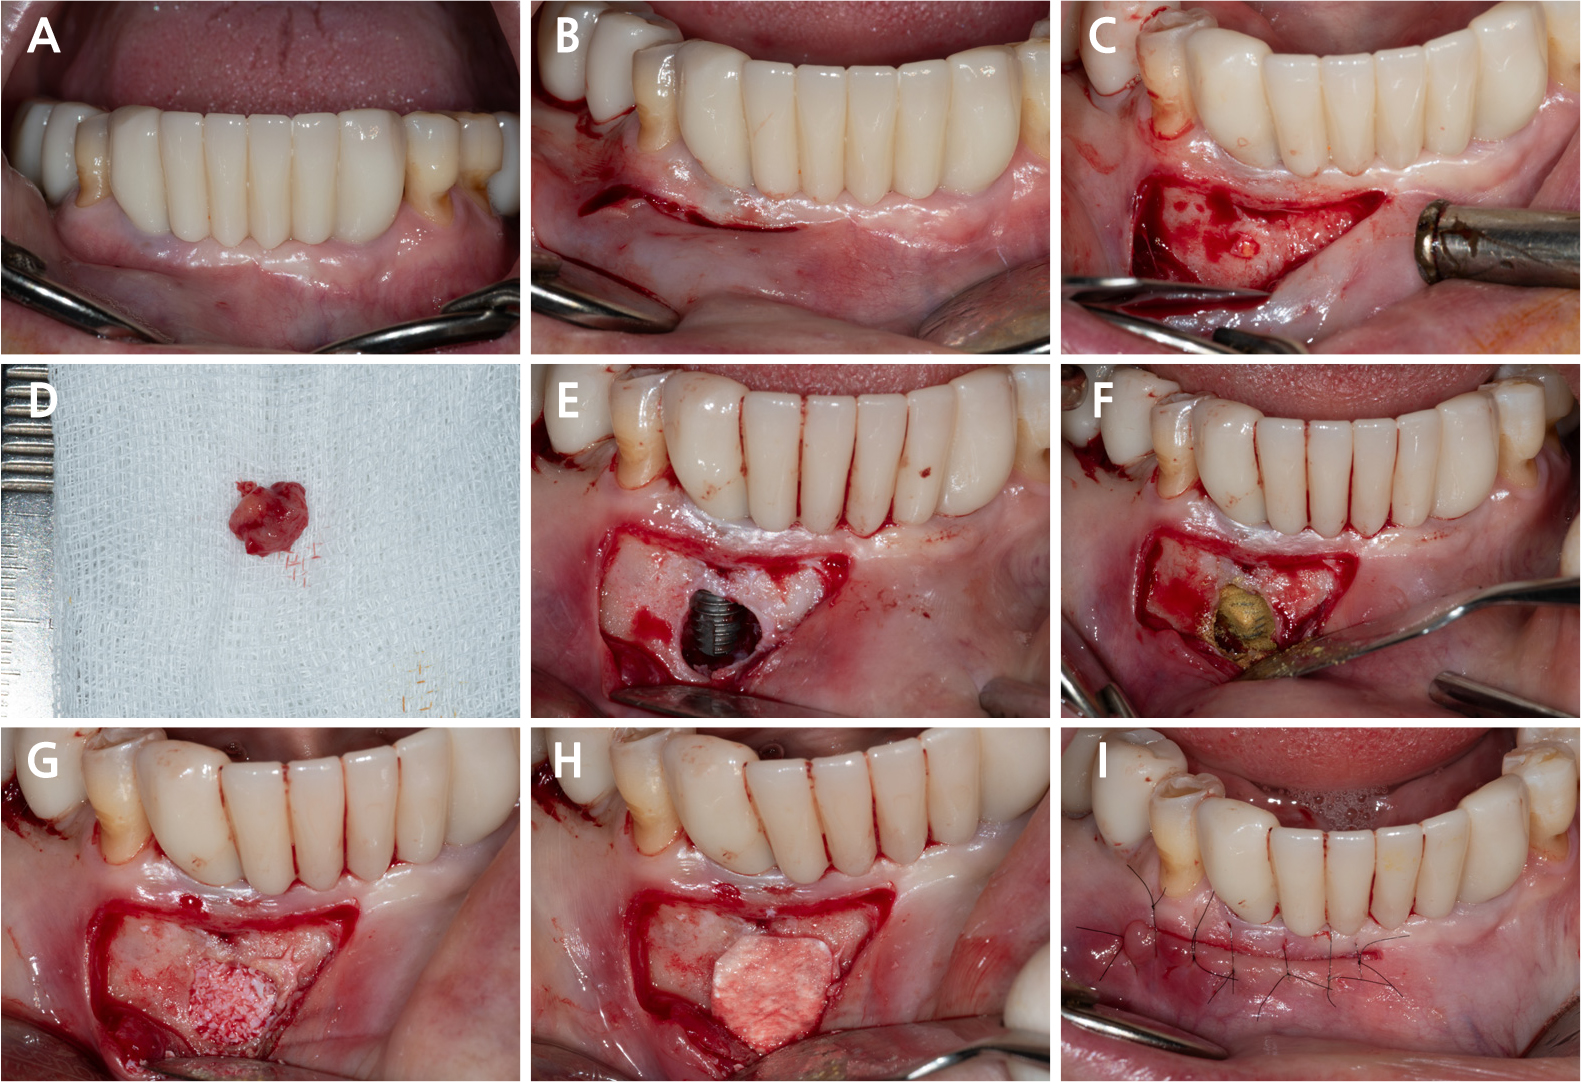

All surgical procedures were performed under local infiltration anesthesia using 2% lidocaine with 1:80,000 epinephrine. Fig. 3A shows the preoperative view. A horizontal incision with a vertical releasing incision at the distal end was made, including one or two adjacent tooth/implant crowns at the mucogingival junction (MGJ), using a #15c blade (Fig. 3B). Following mucoperiosteal flap elevation, the buccal fenestration (Fig. 3C) was apically expanded to approximately ∅5 mm circular window using a diamond drill from a sinus floor elevation kit (DASK Simple kit; Dentium, Suwon, Korea). Granulation tissue was detached and debrided using a surgical curette and hand instruments from the DASK Simple kit (Fig. 3D). The implant surface was decontaminated with a titanium brush (TN brush; Dentium) at 800 rpm under saline irrigation, followed by scrubbing with a cotton pellet soaked in tetracycline hydrochloride for 2 min (Fig. 3E and 3F). The peri-implant bone defect was filled with deproteinized porcine bone mineral (Osteon Xeno; Dentium) and covered with a porcine collagen membrane (Collagen Membrane II; Dentium) (Fig. 3G and 3H). Interrupted sutures were placed using a 6–0 monofilament nylon thread (Ethilon; Ethicon, Somerville, United States) to stabilize the wound (Fig. 3I). The patient was advised to avoid mechanical plaque control at the surgical site and to rinse twice daily with an antiseptic mouthwash (GUM dental rinse; Sunstar, Etoy, Switzerland) for 2 weeks. Antibiotics (clindamycin 150 mg, three tablets daily) and an analgesic (acetaminophen 600 mg, three tablets daily) were prescribed for 5 days to manage postoperative infection and pain. Symptoms resolved following surgery. The wound showed secondary healing at suture removal (2 weeks after surgery) and was fully closed by 4 weeks (Fig. 4). Radiographic bone fill was maintained at the 1.5-year follow-up (Fig. 5).